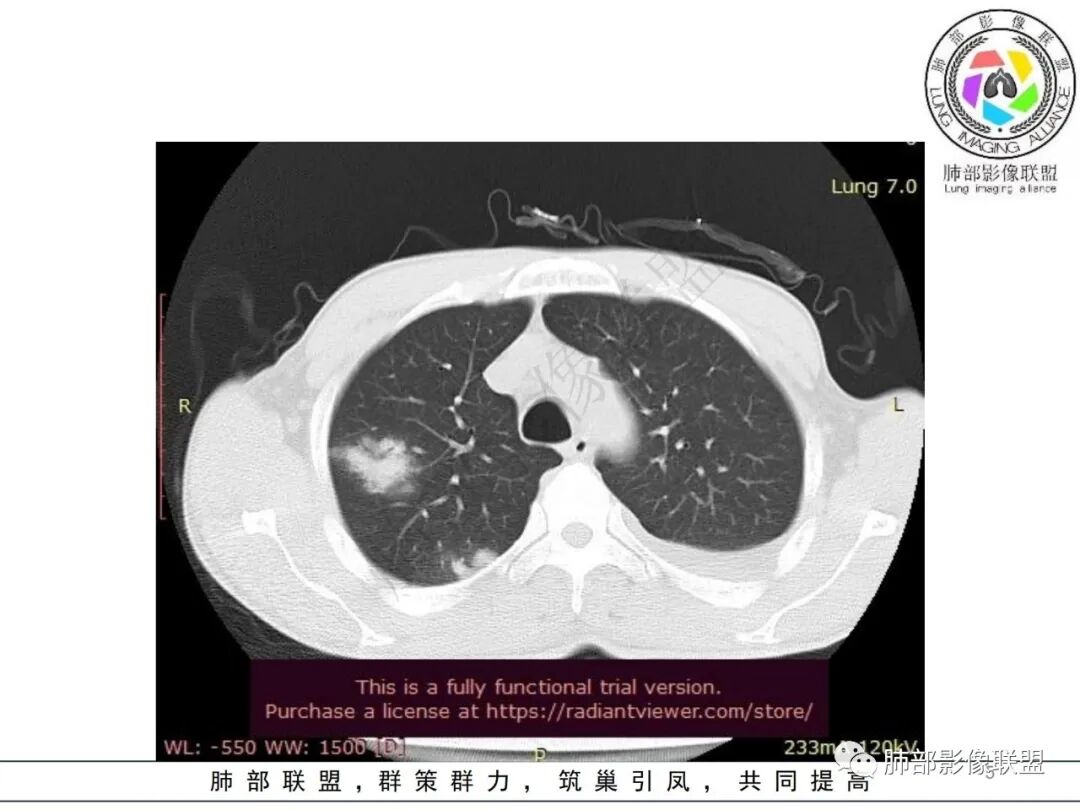

双肺多发大小不等结节影,边缘伴有磨玻璃影,边界欠清,部分与血管束相连,支气管似有穿行病灶内,结节有融合,左肺下叶厚壁空洞,伴有反晕征,左侧胸水,临床中年男性,发热40℃,CRP增高,感染性病变,1:类鼻疽伯克霍尔德菌(好发海南,影像表现也符合)

影像:双肺多发结节、实变影,大部分病灶边界不清,分布相对随机,左下肺坏死空洞形成,伴左侧胸水。

影像表现:双肺弥漫分布斑片影、实变影、磨玻璃影、结节影,晕征、反晕征,随机分布,部分病灶空洞形成前兆,左侧胸腔积液。

两肺多发斑片状实变影,周围GGO

主体还是沿支气管,大片叶段性分布

影像上急性感染,大叶性病变为主

单凭影像:鹦鹉热、军团要考虑,因为内部无坏死,非典型气道为主

影像表现:双肺多发结节、实变影,大部分病灶边界不清,随机分布趋势,左下肺“反晕征”,似有形成空洞趋势。左侧胸腔积液。治疗后复查 ,大部分病灶吸收好转,呈较为典型血播分布,肝脏低密度块影,边界不清,符合肝脓肿。